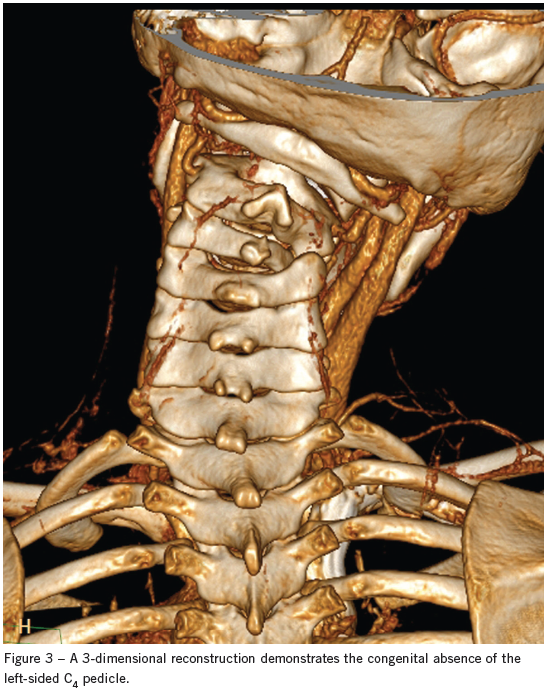

An MRI scan confirmed a unilateral facet dislocation without ligamentous disruption or cord compression. A neurosurgeon evaluated the child, who was admitted to the pediatric ICU for cervical traction and cervical collar placement. He was discharged 3 days later in stable condition. Although no history of trauma was initially given, the mother later stated that the boy wrestled with his brother nearly every day and may have injured his neck at the time of initial presentation. One month later, the child underwent C3-4 diskectomy with anterior fusion of C3-4. At that time he was noted to have congenital absence of the C4 pedicle (Figure 3). He was discharged 2 days after the operation and had no complications.

The absence of a cervical pedicle is a rare congenital anomaly often misdiagnosed as a jumped facet on initial imaging. Patients typically present with pain and spasm after minor trauma, and this may be merely an incidental finding. Misdiagnosis may lead to unnecessary surgical intervention because conservative management is often sufficient.